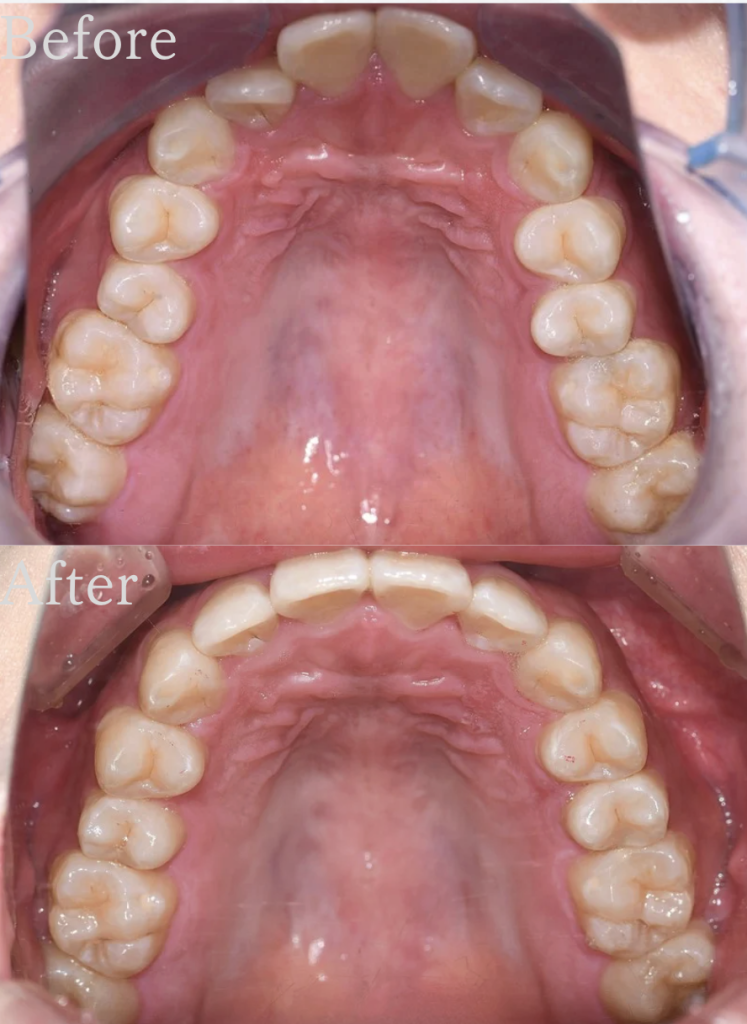

治療計画シュミレーションを作成した結果、

下顎前歯のがたつきはやや大きい数値を示していましたが、抜歯をしたくないという患者様の強いご希望もあり、IPR(歯と歯の間をわずかに削る処置)、遠心移動(奥歯を後ろへ動かす)を

組み合わせてスペースを作成することで、

抜歯を行わずにマウスピース矯正で治療が可能と判断いたしました。

(奥歯を後ろに動かすため、親知らずの抜歯は行う)

また、ディープバイト改善のため、上下の前歯の圧下(顎の骨の中に埋め込む)を行い、適切な前歯の噛み合わせを作りました。

どんどん歯並びがきれいになるのを実感され、矯正終了時には大変喜んでいただけました。